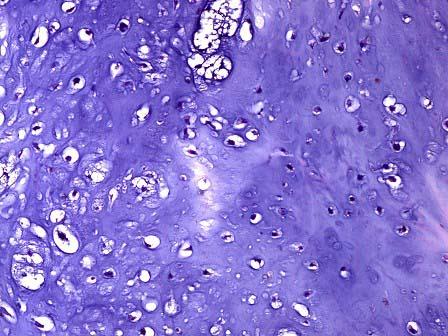

问题 患者,男,21岁,右手示指指骨无痛性肿胀,X线示右手示指指骨骨髓腔内有椭圆的透亮点,呈溶骨破坏。活检见瘤细胞由成熟的透明软骨组成,呈不规则分叶状,由疏松的纤维血管间质包绕,如图1、2所示,该病变的最佳诊断是 ( )

选项 A.骨瘤 B.软骨瘤 C.骨软骨瘤 D.骨囊肿 E.骨样骨瘤

答案 B